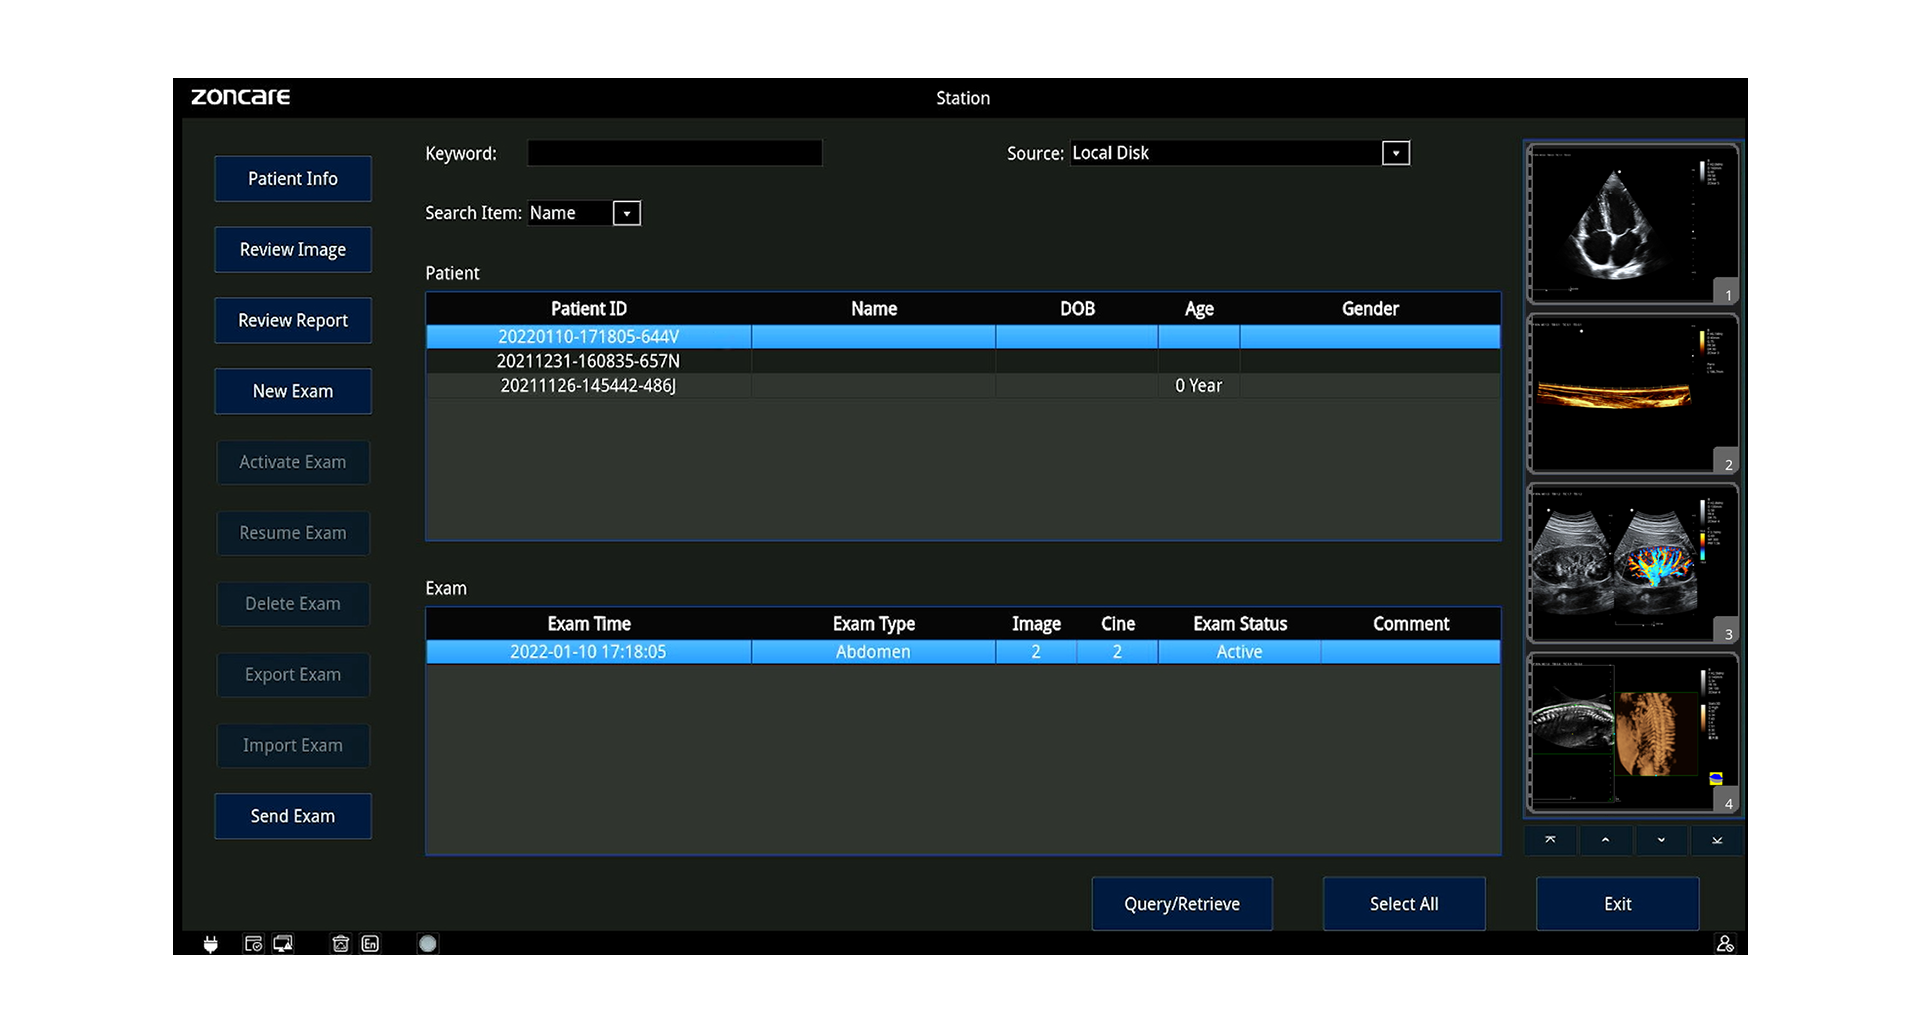

Almacenamiento, Datos y Conectividad

-

Disco interno: 1 TB

-

Formatos: RAW, DICOM, JPG, BMP, TIFF, AVI, MP4

-

DICOM 3.0 (Storage, Worklist, MPPS, Query/Retrieve, etc.)

-

Wi-Fi, Bluetooth, LAN, envío a PC

-

Teleconsulta remota, control inverso y docencia en vivo

-

Informes exportables a PDF (con opción de ocultar datos del paciente)